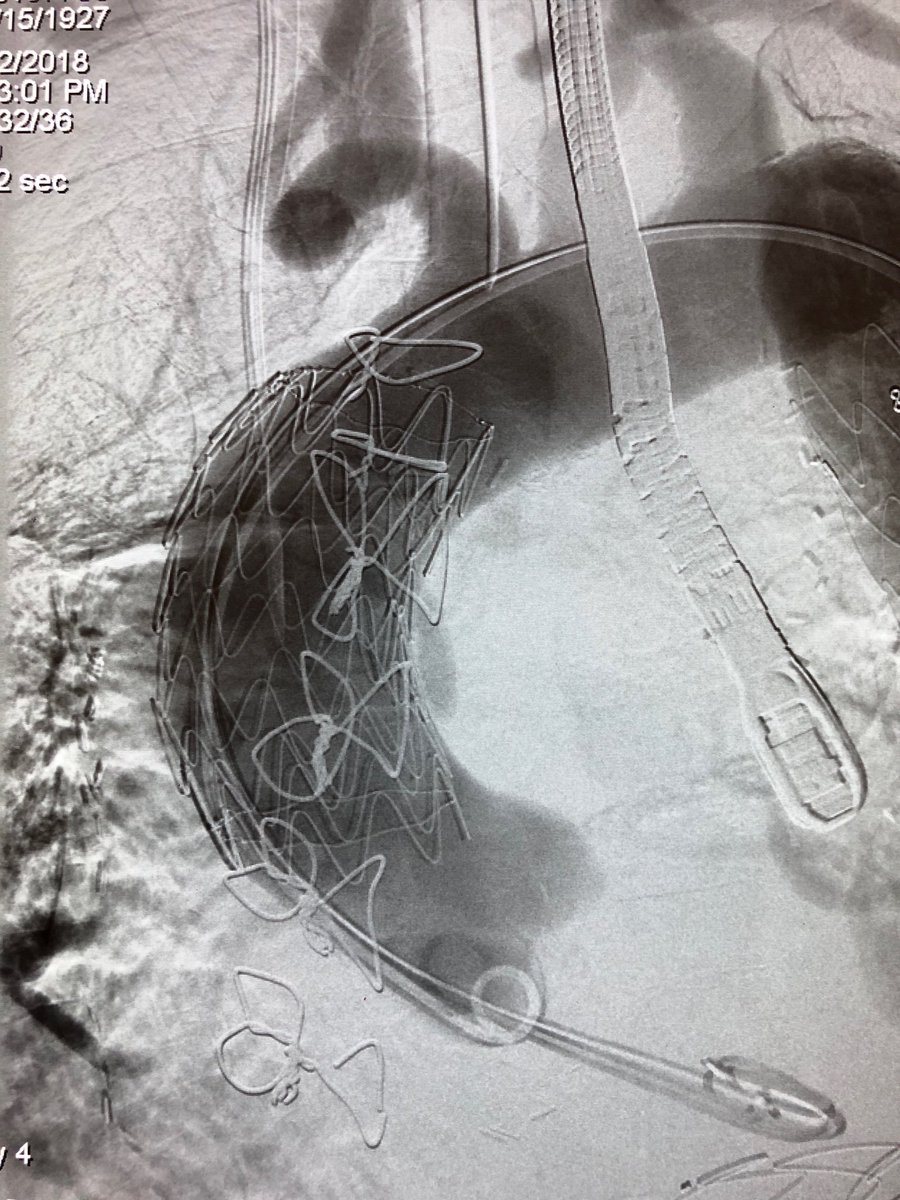

Emergency #TEVAR for #ruptured #typeA #dissection and #aneurysm in #nonagenarian. 1 year follow up #CT shows #healed #aorta #VascularSurgery @CedarsSinai